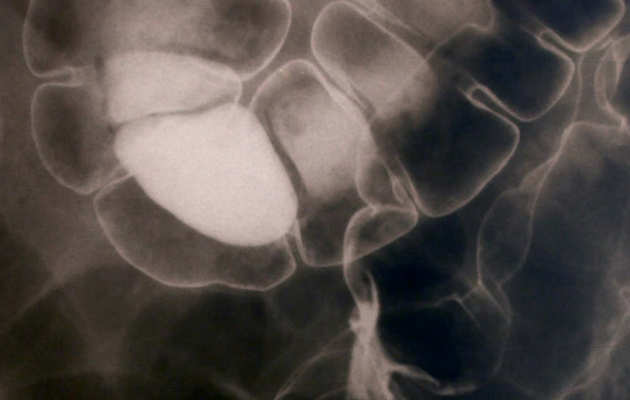

Catching bowel cancer early

A national screening programme to detect the early stages of colorectal cancer - devised by Professor Wendy Atkin - will prevent 3,000 deaths a year once it is fully rolled out.